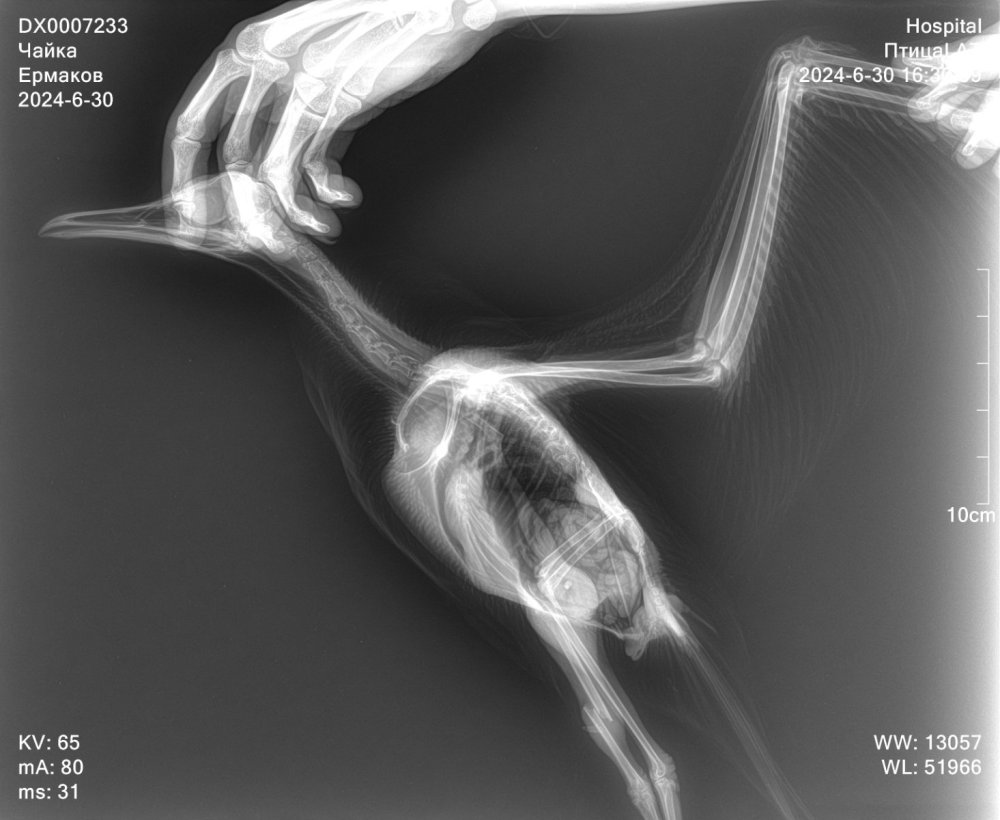

Добрый вечер. Подобрали птенца чайки со сломанной лапкой. Открытый перелом правой лапки. Чайку прооперировали. Поставили спицы. Лапка восстанавливается. Левая лапка была здоровая. Но при транспортировки к орнитологу, что-то случилось с лапкой. Держит в согнутом виде, не выпрямляет и не встает. Делали рентген. На нем нет вывихов и переломов левой лапки. Снимок рентгена перед операцией. повредили левую лапку 29.06.2024 операция правой лапки была 02.07.2024. Данный снимок был сделан 06.07.2024 16.07.2024 делали повторный рентген, чтобы проверить правую лапку после операции. Левую тоже смотрел неоднократно, но никто из врачей не может сказать что с левой лапкой. Подскажите пожалуйста, что может быть с левой лапкой, как восстановить? Для птенца сделаны качели, чтобы снизить нагрузку на лапы.